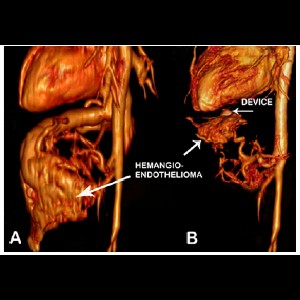

Transcatheter Intervention for Infantile Hepatic Hemangioendothelioma with Amplatzer Duct Occluder II

Transcatheter Intervention for Infantile Hepatic Hemangioendothelioma with Amplatzer Duct Occluder II

Transcatheter Intervention for Infantile Hepatic Hemangioendothelioma with Amplatzer Duct Occluder II

Transcatheter Intervention for Infantile Hepatic Hemangioendothelioma with Amplatzer Duct Occluder II